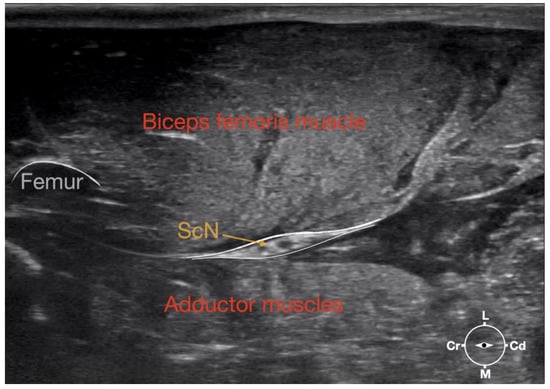

3.1.1. Sciatic Nerve

The ScN emerged between the greater trochanter of the femur and the sciatic tuberosity where its proximal muscular branch was detached from the hamstring muscles. The nerve continued in the distal direction to separate at the level of the distal third of the femur into the tibial and the peroneal nerve. Based on the anatomical dissection and US scans performed in this phase, the best level for injection was determined to be in the proximal third of the femur. At the level of the proximal femur, the sciatic nerve was located caudally to the femur, medially to the biceps femoris muscle, cranially to the semimembranosus, and lateral to the adductor muscles (Figure 7).

Ultrasonographically, the sciatic nerve appeared as a binocular structure with a hyperechoic rim surrounded by the muscular fascias of the biceps femoris and adductor muscles at this level. All muscles were displayed as structures with heterogeneous echogenicity. The biceps femoris muscle was lying lateral to the ScN while the adductor muscle was medial to the ScN. The femur was displayed as a hyperechoic structure with acoustic shadow and located cranial to the ScN nerve.

Figure 1. Corresponding transverse ultrasound image to Figure 2. The ultrasound image shows the sciatic nerve and related structures. The depth was set at 3 cm and the focus was placed at the level of the sciatic nerve. The white lines indicate the muscular fascia enveloping the sciatic nerve. Cr, cranial, Cd, caudal; L, lateral; M, medial.